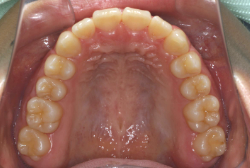

「隙間を閉じたい」という主訴で来院したケースです。診断の結果、「空隙歯列弓+軽度叢生」と判明しましたが、この方の場合は上は隙がある、つまりスペースが余っているのに対して、下は軽度の凸凹がある、つまりスペースが足りないと言う状態でした。

通常、凸凹の症状の場合は、小臼歯を抜歯させていただくのですが、この方の場合は凸凹も軽度で親知らずもないため、非抜歯で対応することになりました。マルチブラケット装置にて治療を開始し、治療期間は11ヶ月でした。治療後は正中の空隙が閉鎖されただけでなく、下の凸凹と下の歯並びの形態そのものが大幅に改善されました。もちろん噛み合わせ的にも正しい状態が確立しています。